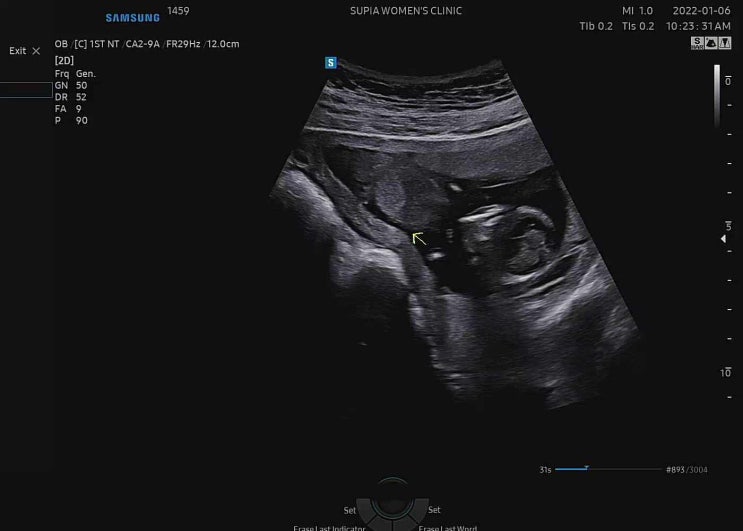

임신 기록_16주 2차 기형아 검사, 성별 공개?

어느새 무럭무럭 자라 16주! 임신 5개월이라니요 ? 딩크로 살까 1명만 낳을까 고민 많이 했는데, 갑작스...

임신 기록_13주 태아보험, 1차 기형아 검사

8주에 방문했을 때 자궁 안에 피고임도 사라졌고, 아기도 안정적으로 잘 크고 있어 다음 방문은 4주 후라고...